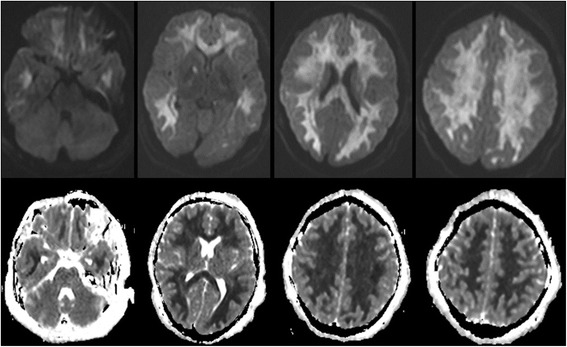

In the fifth day of admission, he was found to have fixed dilated left pupil and normal reactive right one. His level of consciousness was the same. Physical examination showed generalized hypotonia with bilateral extensor plantar responses. Intravenous mannitol was given and urgent CT scan of the brain showed a clear generalized diffuse hypodensity involving the subcortical white matter (Figure 1B). MRI brain done in the 7th day of admission which showed diffuse white matter changes with sparing of the brain stem and cerebellum (Figures 2 and 3).

The MRI findings in our case shows extensive selective white matter damage with sparing of the gray matter. Strikingly, the brainstem and cerebellum were totally spared. Such findings resemble the cases of delayed post hypoxic leukoencephalopathy related to carbon monoxide or opioids overdose. The findings were more pronounced in the diffusion MRI sequences which suggest an acuteness of the illness.

The characteristic MRI findings in DPHL include diffuse white matter hyperintensities on T2 sequences involving the periventricular white matter bilaterally which is diffuse and involves bilateral centrum semiovale areas [ref. 10,ref. 11,ref. 20]. Classically, in cases of DPHL, these lesions are restricted to the periventricular subcortical white matter, sparing the cerebellum or the brain stem [ref. 4,ref. 6,ref. 7,ref. 13,ref. 16,ref. 19] and doesn’t enhance after contrast administration. On diffusion weighted imaging (DWI), there is a symmetric decrease in the apparent diffusion coefficient (ADC) values in the corona radiata and the centrum semiovale white matter [ref. 15]. In addition to areas of restricted water diffusion in both globus pallidi which are usually evident as hypodensities in CT scan [ref. 4]. DPHL Cases caused by carbon monoxide poisoning had also the same involvement of periventricular white matter, centrum semiovale and also sparing of the infratentorial structures [ref. 2]. This finding might help in differentiating DPHL from the chronic heroin vapor inhalation leukoencephalopathy (chasing-the-dragon toxicity) where there is usually involvement of the infratentorial structures, mainly brainstem and cerebellum [ref. 4,ref. 21].